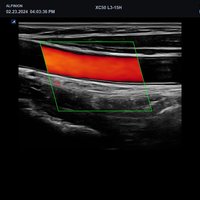

• Gefäße

• L3-15H (3-15 MHz) für Ultraschalluntersuchungen in den Bereichen Gefäße, Weichteile, Bewegungsapparat (MSK)

• L3-12H WD (3-12 MHz) für Ultraschalluntersuchungen in den Bereichen Gefäße, Weichteile, Bewegungsapparat (MSK), Pädiatrie

• L3-8H (3-8 MHz) für Ultraschalluntersuchungen in den Bereichen Gefäße, Bewegungsapparat (MSK), Pädiatrie